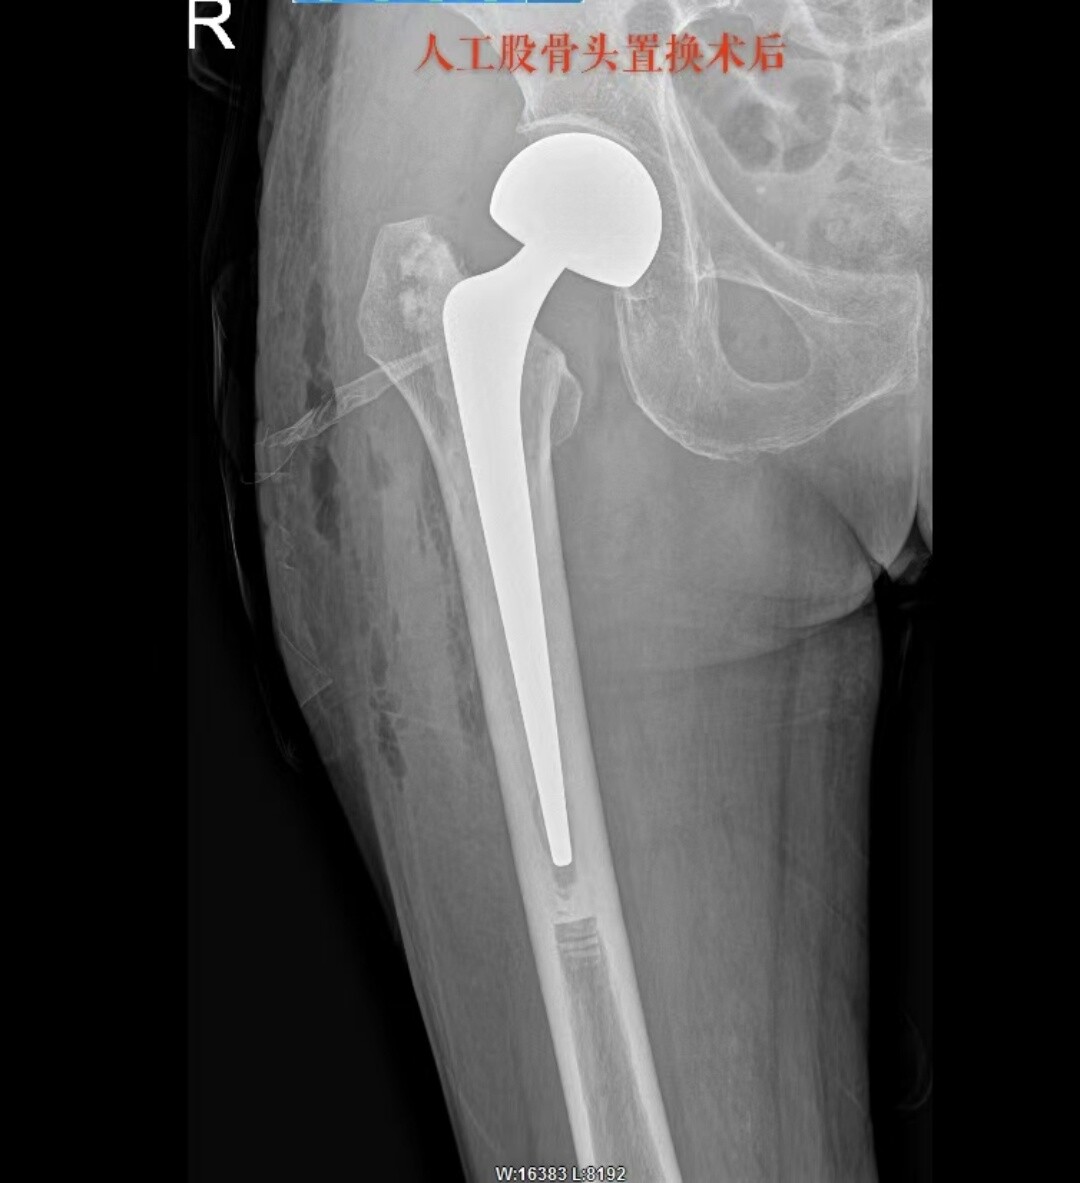

81 岁患者的朱奶奶,因摔伤致右髋部疼痛 2 天入院,确诊为右侧股骨颈骨折。永兴县人民医院骨二科团队在充分评估朱奶奶的病情后,决定采用 “保留梨状肌人工股骨头置换术”,术后第一天,朱奶奶便在医护人员的保护下顺利下地站立并行走,疼痛感明显减轻,关节活动功能恢复良好。

永兴县人民医院骨二科团队率先引进并成熟开展多例 “保留梨状肌的人工股骨头置换术”,采用改良后外侧小切口入路。在医生最熟悉的后外侧入路基础上进行改良。通过采用更小的切口(约5-8cm)和更精细的软组织分离技术,在不切断梨状肌及其附着点的前提下,借助人体自然的肌肉间隙——梨状肌和臀小肌之间的缝隙进入关节,巧妙地暴露手术视野,显露髋关节囊,精准植入假体,完整保留髋关节的后方稳定结构。